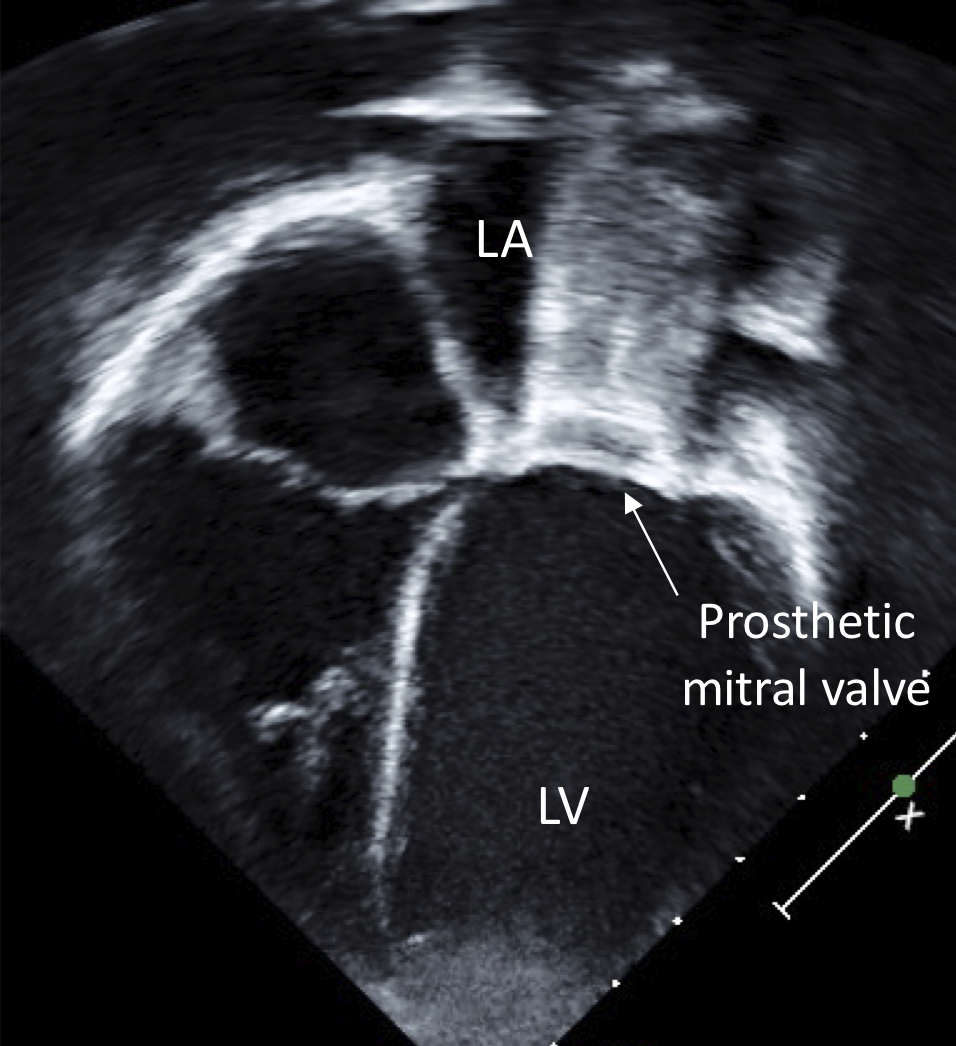

- Strong reflection is desirable from the structures that are to be imaged, but causes problems if it prevents the ultrasound beam from reaching the structures of interest. For example, prosthetic valves are strong reflectors and can conceal (“shadow”) structures behind them, as shown in Fig. 4.

Figure 4. This apical 4 chamber view of a patient who has had the mitral valve replaced with a prosthetic valve shows “shadowing” of the left atrium from the prosthesis, such that one cannot evaluate the left atrium. LV, left ventricle; LA, left atrium. - At air-tissue interfaces, due to the density difference, nearly all ultrasound is reflected, so very little is transmitted. (Ultrasound is also rapidly attenuated in air.)